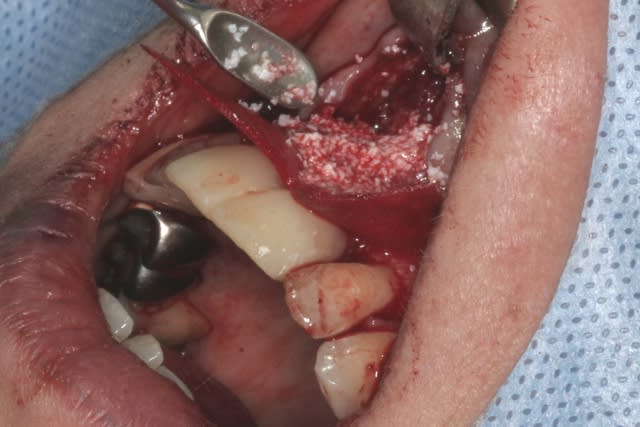

tien, ce matin, extraction de 24/25, curetage méticuleux, forage, comblement du gap, pose des 2 implants qui se sont bloqués à 50Ncm au CA sur les 3 ou 4 mm apicaux, pose des vis de cicat, sutures...35min....tranquille...

12/06/2014 à 13h50

Purée, tu prends des risques énormes en fourrant ton bio oss puis en vissant les implants dans la masse de bio oss, de un, et sans membraner l'interface pilier implant, de deux...

Je suis peut-être vieux jeu mais c'est, à mon avis, dangereux d'un point de vue bactériologique.

Photo pluton1b h9n4ea - Eugenol

pluton

12/06/2014 à 13h55

c'est pas la première fois que je fais çà...;-)

et çà me donne plutôt de bons résultats

après tout...le périoste n'est-il pas la meilleure membrane?

par contre il faut veiller à avoir une bonne étanchéité au niveau des sutures...